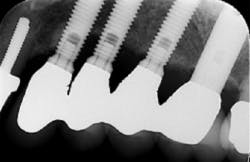

Let’s first start by examining the shape of an implant bridge in comparison to one supported by natural teeth. Since implants have a smaller circumference at the neck of the crown, “teeth” in bridgework can appear narrower and with large embrasures depending on the width of the area being restored. The restoration can appear round and bulky, or with elongated crown margins.(1) If there is recession in any of these instances, access to the exposed threads can become impossible. A poorly contoured restoration may inhibit the patients’ ability to control biofilm at the gingival margin increasing the risk for peri-implant diseases.(1,3) Brushes that can reach the gingival margin and/or the body of the implant (if exposed) make for a more effective home care regime.